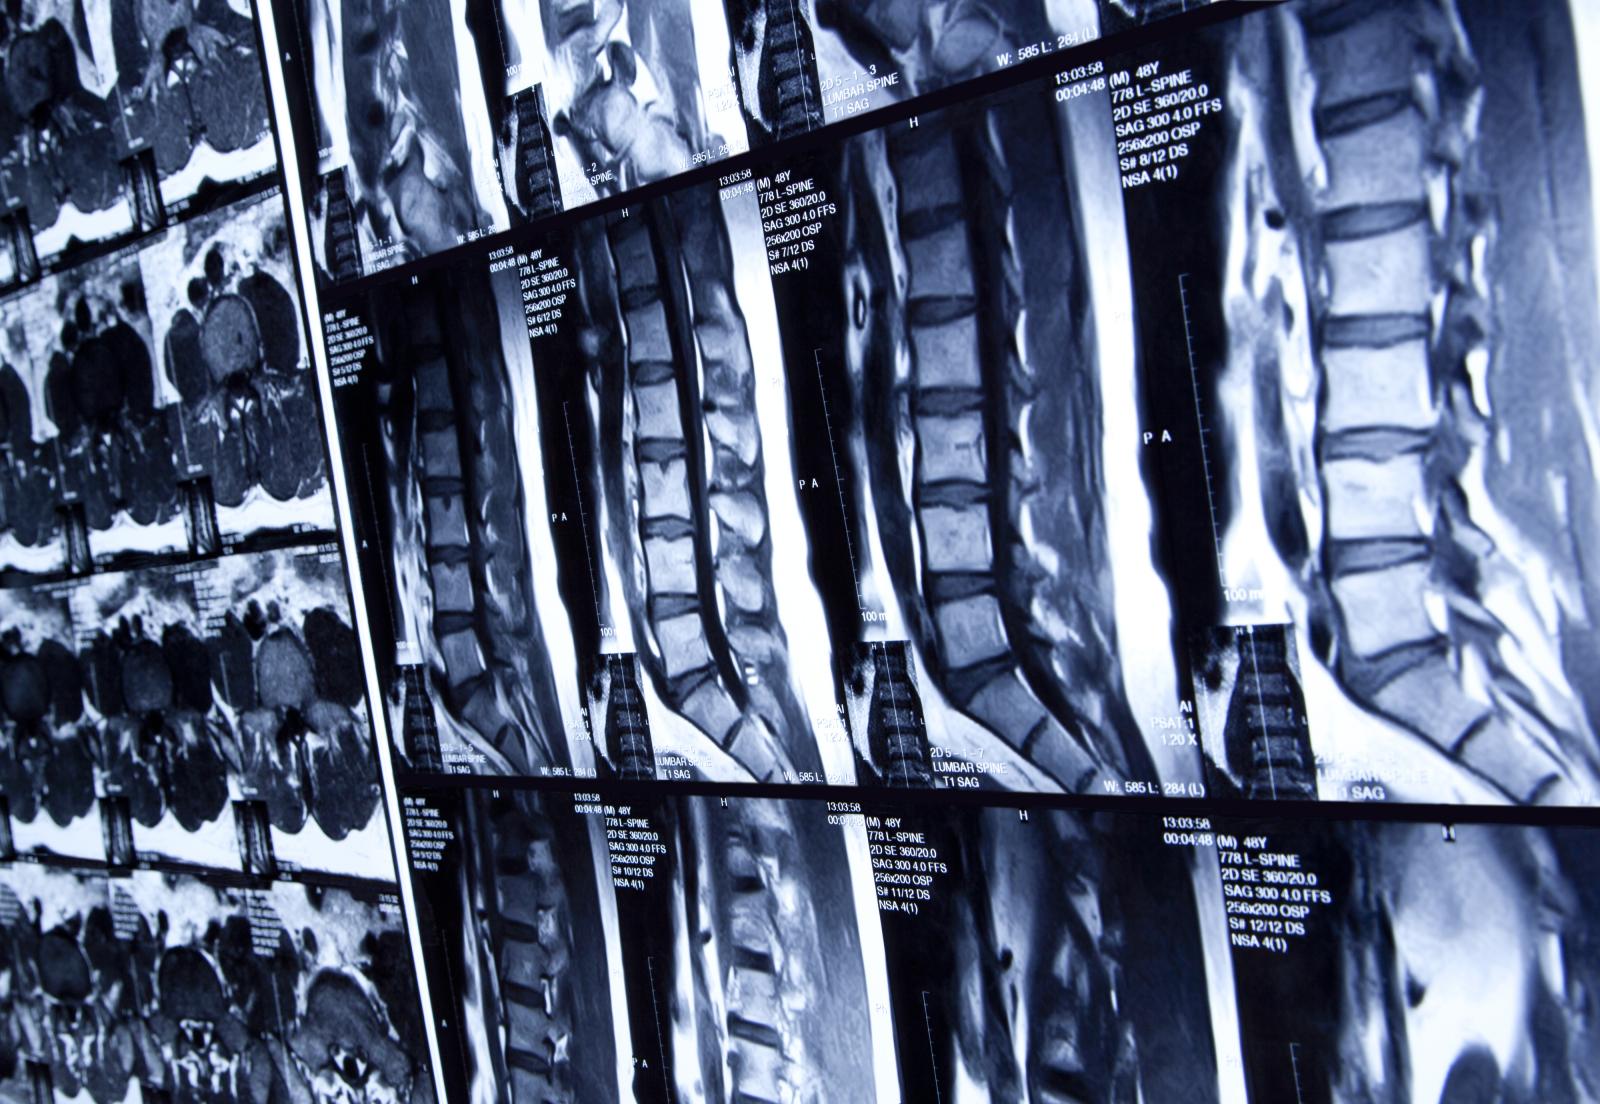

Hidden spine fractures, affecting around 2.2 million people in the UK, could be detected earlier thanks to new draft guidance from NICE, which recommends adding a vertebral fracture assessment to routine bone scans.

Currently, 70% of spine fractures caused by osteoporosis go undiagnosed, as they often present no obvious symptoms initially. Adding a quick spine check during dual-energy X-ray absorptiometry (DXA) scans takes just a few minutes and could prevent significant pain and disability later in life.

The draft guideline, now open for consultation, advises healthcare practitioners to consider offering VFA during DXA scans for people aged 50 and over. Evidence shows this is cost-effective, as it can be performed on the same scanner during the same visit.